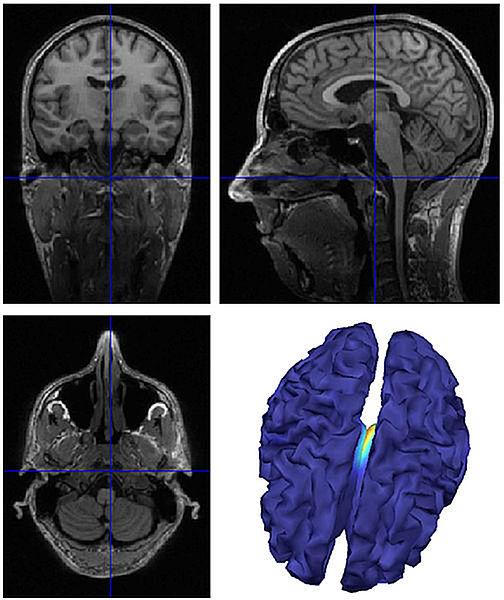

La técnica permite detectar focos epilépticos. (Foto: Jorge Iván Padilla Buriticá)

“Durante el proceso implementamos una técnica conocida como ‘elementos finitos de frontera’ para obtener una estructura del cerebro similar a la lograda durante la resonancia magnética que se le practica a cada paciente”, argumenta el magíster.

El procedimiento está diseñado para que el especialista no necesite ajustar parámetros relacionados con la ingeniería, solo debe alimentar el software con señales reales y datos del paciente, que luego son mapeados e incluidos en la resonancia magnética. Así, resulta una medición más fácil de interpretar por el médico.

Según el investigador, “la verificación se adelanta simulando la actividad dentro del cerebro, lo cual ofrece confiabilidad y efectividad en el método para determinar exactamente el punto que se está activando”.